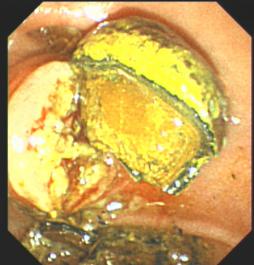

8. 內(nèi)鏡下消化道異物取出術(shù)